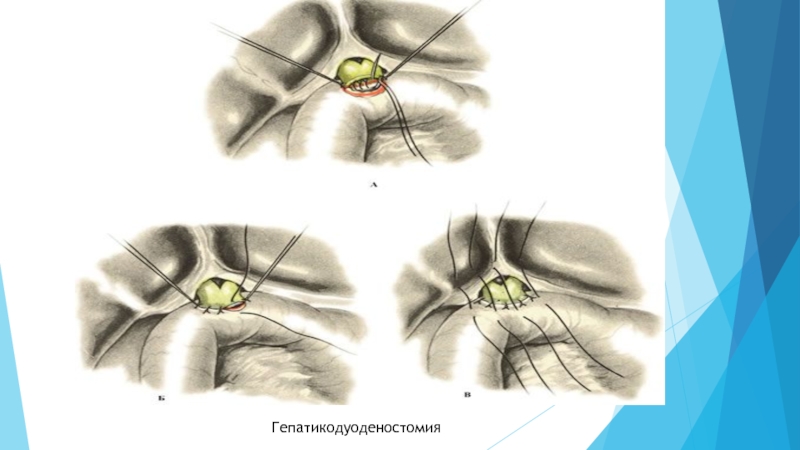

Слайд 616) Наложение обходных билиодигестивных анастомозов

Обычно применяются при опухолевых поражениях панкреатодуоденальной

зоны либо при протяженных рубцовых сужениях протоков. При высоких рубцовых стриктурах

желчных протоков выполняют сложные реконструктивные операции, направленные на восстановление оттока желчи. Среди них наибольшее распространение получили билиодигестивные соустья на различных уровнях желчных протоков с петлей тонкой кишки, выключенной по Ру (холедохоеюностомия). При опухолевых поражениях после ликвидации желтухи малоинвазивным способом выполняют радикальное или паллиативное хирургическое вмешательство. Возможность выполнения радикальной операции у таких пациентов отмечается не более чем в 15-20% случаев. Радикальные операции заключаются в резекции зоны, пораженной опухолевым процессом (холедоха, панкреатодуоденальная резекция) с формированием гепатикоеюноанастомоза. Паллиативные операции направлены на создание обходных билиодигесивных соустий. В случае рака головки поджелудочной железы операцией выбора является холецистоэнтеростломия по Микуличу. Условие успешной декомпрессии желчных путей при этой операции - проходимость пузырного протока. При других локализациях опухоли формируют билиодигестивные соустья (гепатикоеюноанастомоз, чем выше, тем лучше) либо применяют один из способов эндопротезирования. Гепатикоеюноанастомоз (к общему желчному протоку пришивают тонкую кишку) имеет наиболее широкие показания. При этом виде анастомоза в соустье с тонкой кишкой может участвовать как общий печеночный проток, так и печеночные протоки более мелкого калибра. Анастомоз формируется с мобилизованной по Ру петлей тощей кишки (длиной 40-60 см). Формирование гепатикоеюноанастомоза на выделенной по Ру петле тощей кишки практически исключает рецидив механической желтухи и гнойного холангита в позднем послеоперационном периоде. Анастомоз предпочтителен среди больных с нерезектабельными билиопанкреатобилиарными опухолями, осложненными механической желтухой.

Слайд 63Гепатикодуоденостомия

Гепатикодуоденостомия